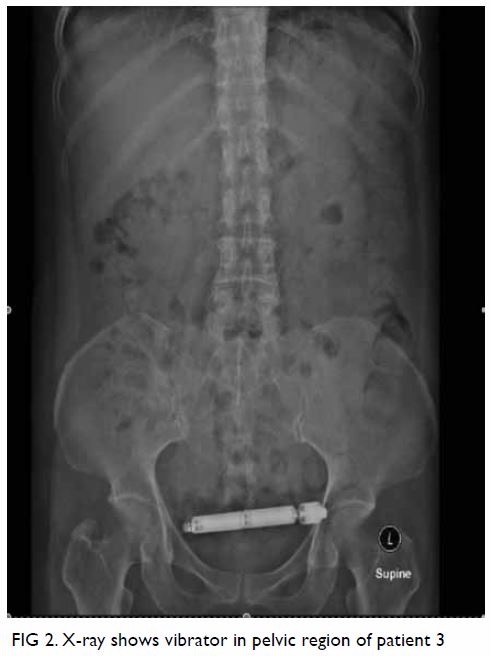

Фото 2НемедицинаFigure 2. Рентгеновский снимок визуализирующий вибратор в области таза пациента Немедицина